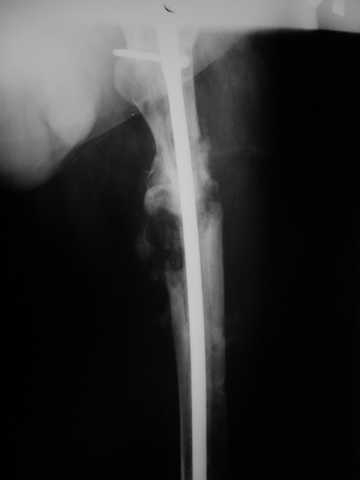

Мы демонтировали спице-стержневой аппарат, рассверлили костно-мозговой канал (до 14 мм), установили в канал спейсер с антибиотиком и произвели его блокирование четырьмя винтами ( рис. 1, 2, 3, 4).

В качестве армирующего элемента для спейсера мы использовали титановый неканюлированный штифт типа UFN (диаметр 9 мм, длина 400 мм). Проксимальную широкую часть штифта костным цементом не покрывали (рис. 5).

Дистальные блокирующие отверстия в цементе рассверлили после его застывания под ЭОП'ом. В проксимальном отломке использовали винт-полер (так как штифт проходил очень близко к переднему кортикальному слою).

В остальном, операция прошла без технических трудностей. Александр Николаевич, спасибо за ваши прекрасные развертки. Так не хочется отдавать их Вам обратно! Завтра пациент выписывается. Температура тела и анализы у него нормальные. Бедро мягкое, отечность тканей значительно уменьшилась. Послеоперационные раны зажили первичным натяжением. Укорочение конечности составляет 1,5 см (по ощущениям больного, это оптимальная длина ноги для него, так как у него анкилоз коленного сустава и голеностопного сустава в положении подошвенного сгибания). Пациент ходит с дозированной нагрузкой на конечность (10% от веса тела). Свищ на передне-наружной поверхности средней трети бедра, который открылся за неделю до последней операции рядом со стержнем аппарата, закрылся 5 дней назад (рис. 6,7, 8).